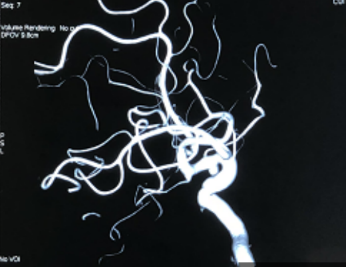

治疗过程:患者多参数监护仪监测下,全麻满意后,常规消毒铺巾,采用改良Seldinger技术穿刺右侧股动脉成功,置入8F动脉鞘。经右侧股动脉鞘,黑泥鳅带领长鞘(Penumbra Neuro MAX6F )到达右侧颈内动脉岩段,撤下泥鳅导丝,微导丝(Synchro 0.014 in*200 cm)带领支架微导管(Prowler Select Plus)达右大脑中动脉M1段,撤出微导丝,再次用微导丝(Synchro 0.014 in*200 cm)带领微导管(Echelon10eV3)超选到达眼动脉段动脉瘤内,退出微导丝。经Echelon10微导管送入(Codman COMPLEX XTRASOFT 3 mm×8 cm)弹簧圈一枚成篮并未解脱,后经支架微导管释放支架一枚(Codman ENTERPRISE 4.5 mm*22 mm)支架打开良好,覆盖瘤颈,撤出支架微导管后解脱首枚弹簧圈,复查造影,弹簧圈位置形态良好,解脱后继续送入(Codman COMPLEXXTRASOFT 2.5 mm×3.5 cm; EV3 3D 1 mm×2 cm;EV3 3D 1.5 mm×4 cm)3枚弹簧圈,期间间断造影确保眼动脉段血流通畅,栓塞后复查脑血管造影,动脉瘤区未见显影,未见造影剂渗漏。手术结束。缝合器缝合右股动脉穿刺点,加压包扎。术后患者麻醉清醒,拔除气管插管,呼唤应答,对答切题,言语清楚,四肢肌力肌张力正常。

动脉瘤大小

术中栓塞: